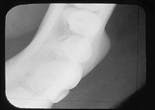

Case 2

Osteoma

1. Identify the most common location for the osteoma.

a. anterior mandible

b. angle of the mandible

c. anterior maxilla

d. posterior maxilla

e. none of the above

2. Identify the radiographic appearance of the osteoma.

a. radiolucent

b. radiopaque

c. mixed lucent/opaque

d. radiolucent or radiopaque

3. Identify the treatment of choice for the osteoma.

a. none

b. cryosurgery

c. surgical excision

d. electrosurgery

e. radiation therapy

4. Identify the TRUE statement concerning the osteoma.

a. often occurs in children

b. often occurs in multiples

c. often involves the maxilla

d. often asymptomatic

e. often fast-growing

CASE 2: 1 = b; 2 = b; 3 = c; 4 = d